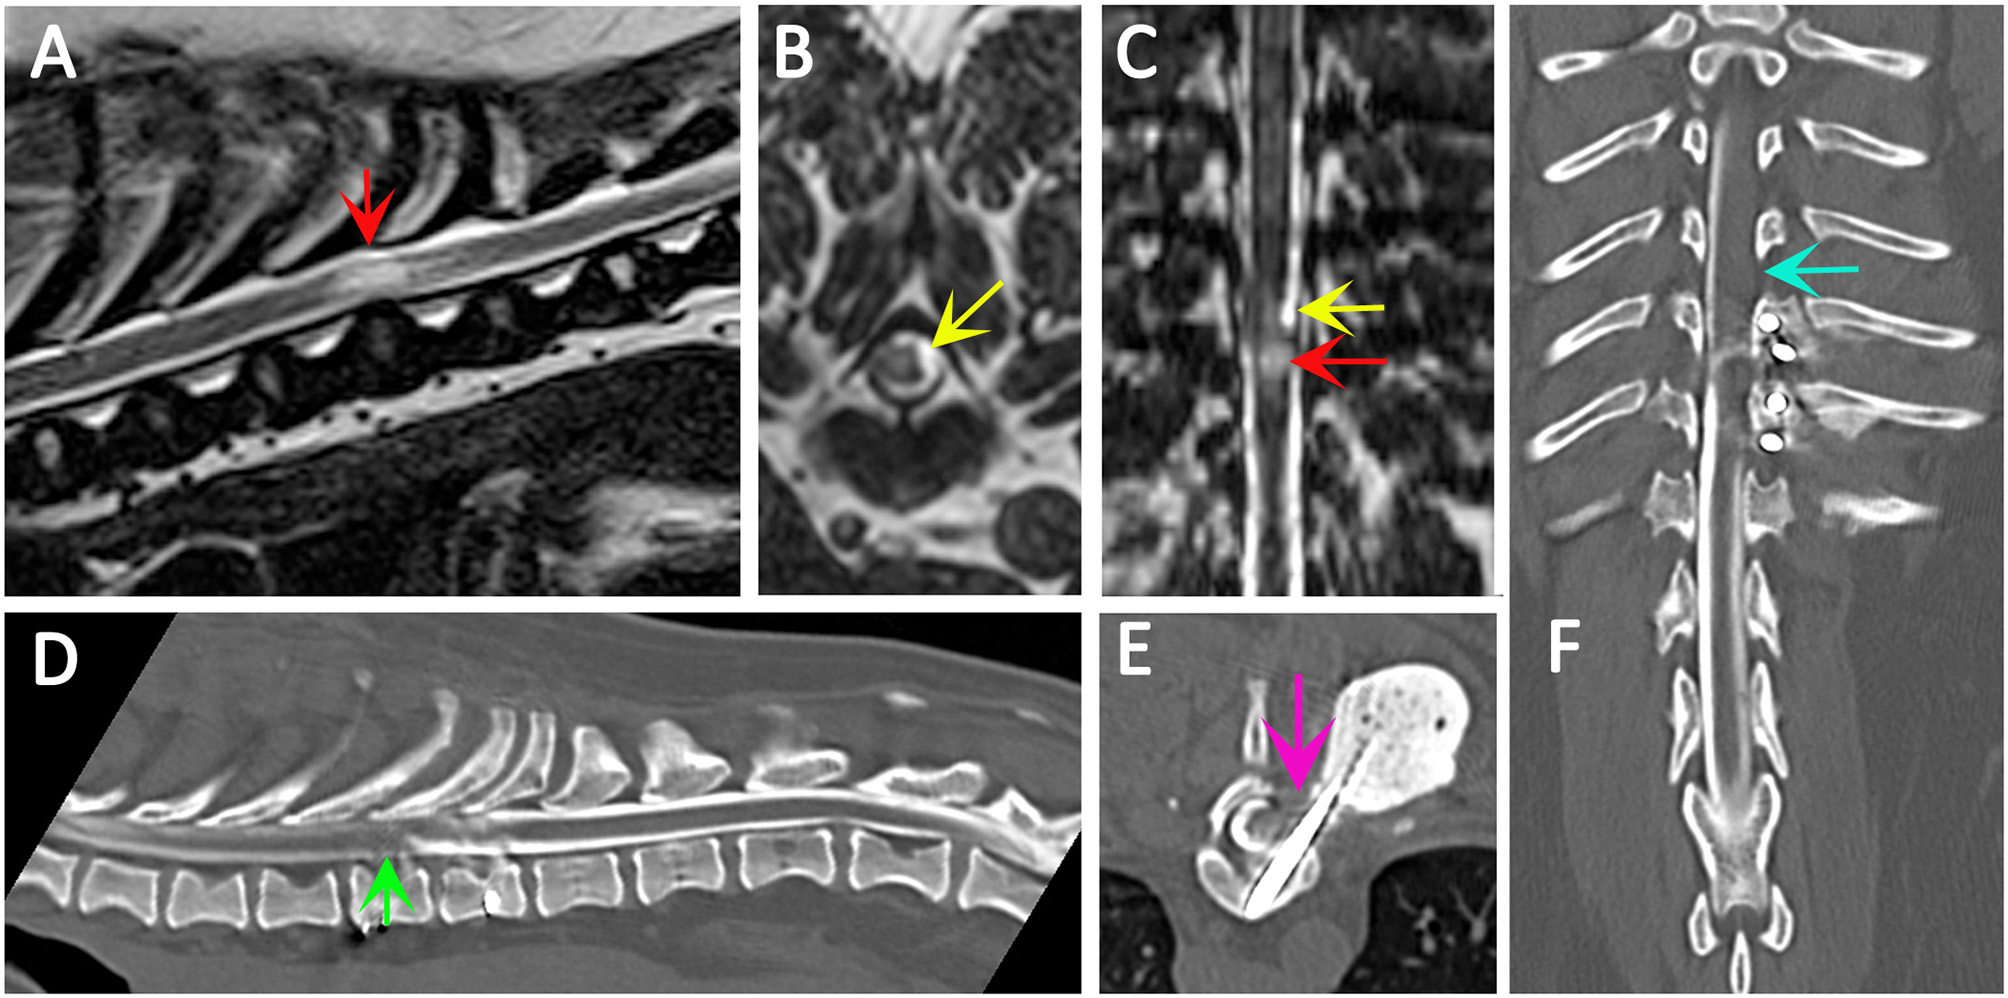

Figure 4

Use of CT myelography to investigate arachnoid adhesions in in a 10 year old female Pug dog presented with signs of a thoracic myelopathy and that had previous surgical management for spinal arachnoid diverticulum and vertebral instability. Six months previous this dog had previously been managed surgically for a spinal arachnoid diverticulum (red arrow) with associated spinal cord edema/presyrinx (yellow arrow) at the level of T9/T10. She had been presented originally with a 2 year progressive history of myelopathy and the arachnoid diverticulum was considered associated with vertebral instability. Surgical management included marsupialization of the arachnoid diverticulum and spinal stabilization with Interface Pins (IMEX Veterinary Inc, Long View Texas) and Simplex-tobramycin bone cement (Howmedica, Limerick, Ireland). After an initial improvement the dog deteriorated and the metal implant precluded repeat MRI. CT myelography was performed from a lumbar injection. There is a reduced flow of contrast cranially (green arrow) and block to flow of the contrast material on the left side (blue arrow) and transverse images suggest adhesions between the spinal cord tissue and laminectomy site confirmed at surgery (pink arrow). (A) T2-weighted mid-sagittal MRI of the spinal cord from T6 to L1. There is a focal area of spinal cord edema (presyrinx) at the level of T9/T10 (red arrow). (B) Transverse 3D-CISS image at the level of T9/T10. There is a focal dilatation of the subarachnoid space at T9/T10 (yellow arrow). (C) Dorsal 3D-CISS image at the level of T7 to T13 demonstrating spinal cord edema (presyrinx) at the level of T9/T10 (red arrow) and suspected arachnoid diverticulum cranial to it (yellow arrow). (D) Midsagittal computed tomographic myelography from T6 to L2; there is reduced flow of iodinated contrast material cranial to T9 (green arrow). (E) transverse computed tomographic myelopathy at the level of T9. There is an adhesion between the spinal cord and laminectomy site (pink arrow). (F) Dorsal computed tomographic myelography from T6 to L2; there is a block of iodinated contrast material cranial to T9 (blue arrow) (Siemens Magnetom Symphony, A Tim System, 1.5 T, Erlangen, Germany; Toshiba Aquilion Prime 160 slice, Otawara, Japan). Image acknowledgment Dr Anna Tauro and Dr Colin Driver, Fitzpatrick Referrals.